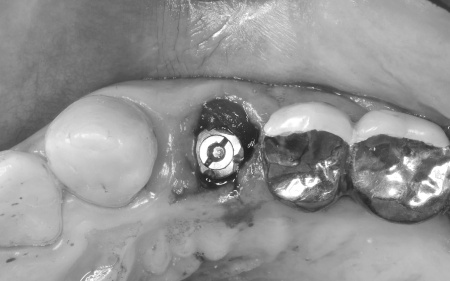

診断結果をお伝えし、患者様の了承を得たうえで左下奥歯の被せ物を外したところ、レントゲン検査での診断どおり、歯根が割れていることが確認できました。

まず、左上下奥歯を慎重に抜きます。

続いてインプラント手術を実施し、インプラントを正しい位置と角度で顎の骨に埋め込みました。